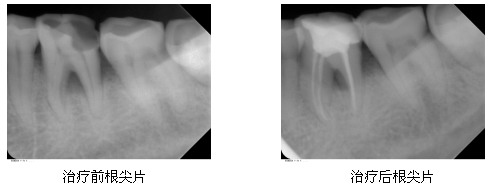

以下是一名52岁的女性患者左下后牙根管治疗的病例,患者因左下后牙自发痛3天,冷热刺激加剧前来就诊,经临床检查确诊为左下第一磨牙龋齿引起的急性牙髓炎,需做根管治疗。因患者年龄较大,根管存在钙化,而且牙根形态弯曲,治疗难度较大,经过仔细探察,运用先进的仪器设备,做到完善根充,治疗效果理想,症状完全消失。治疗前后根尖片见图。